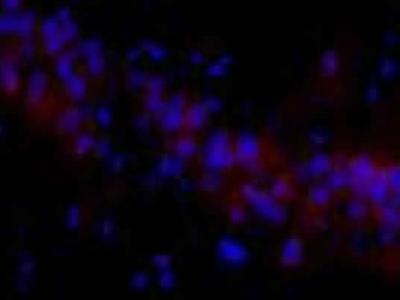

孕期乙醇暴露大鼠的子鼠海马组织中细胞周期性蛋白激酶5荧光染色的神经元数量较多...